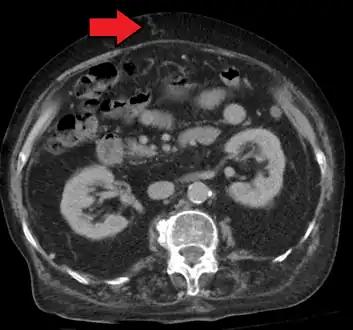

In addition, a widened (dilated) portal vein as seen on a CT scan or MRI may raise the suspicion about portal hypertension. A cutoff value of 13 mm is widely used in this regard, but the diameter is often larger than this is in normal individuals as well.[7]

-

Magnetic resonance imaging of portal hypertension -

Portal hypertension due to cirrhosis resulting in revascularization of the umbilical vein

Ultrasonography (US) is the first-line imaging technique for the diagnosis and follow-up of portal hypertension because it is non-invasive, low-cost and can be performed on-site.[12]

A dilated portal vein (diameter of greater than 13 or 15 mm) is a sign of portal hypertension, with a sensitivity estimated at 12.5% or 40%.[13] On Doppler ultrasonography, a slow velocity of <16 cm/s in addition to dilatation in the main portal vein are diagnostic of portal hypertension.[14] Other signs of portal hypertension on ultrasound include a portal flow mean velocity of less than 12 cm/s, porto–systemic collateral veins (patent paraumbilical vein, spleno–renal collaterals and dilated left and short gastric veins), splenomegaly and signs of cirrhosis (including nodularity of the liver surface).[12]

The hepatic venous pressure gradient (HVPG) measurement has been accepted as the gold standard for assessing the severity of portal hypertension. Portal hypertension is defined as HVPG greater than or equal to 5 mm Hg and is considered to be clinically significant when HVPG exceeds 10 to 12 mm Hg.[15]